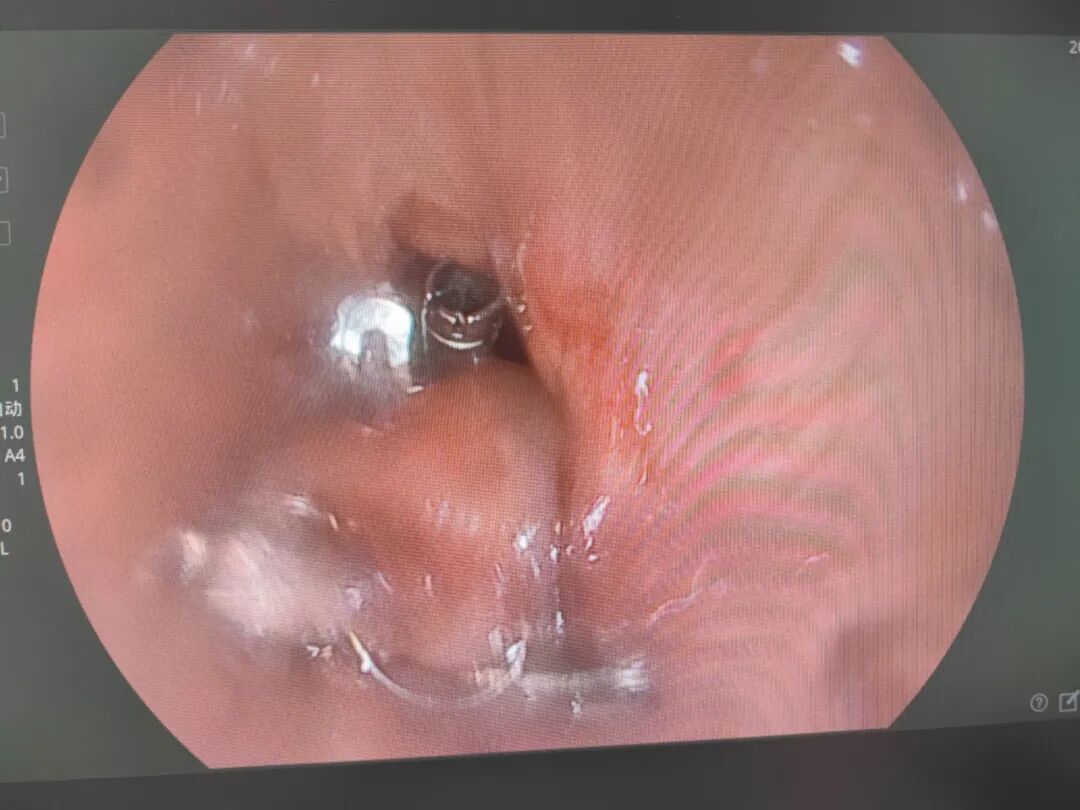

术前